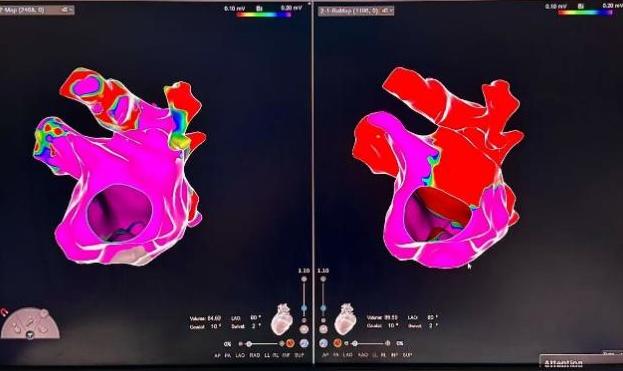

周某,78岁,长期受到持续性房颤的困扰,合并冠心病、高血压,并有一次卒中史,病程长达十余年。起初,症状表现为偶发的心悸和胸闷,但近几年症状逐渐加重,发展为频繁气短、乏力,严重影响了日常生活。考虑到他的卒中史以及房颤带来的潜在风险,且曾因心脏功能异常植入过起搏器,周爷爷的治疗方案在兰州大学第一医院心血管团队的精心制定下,采取了个性化的综合治疗方案,不仅通过先进的脉冲消融术精准处理房颤,还结合其卒中风险高的特点,施行了经皮左心耳封堵术,从源头预防卒中发生,为患者提供全方位保护。这一双管齐下的治疗策略,不仅显著改善了心律失常,还为患者的未来健康筑起了一道坚实的屏障。

FARAPULSE导管花瓣消融

左心耳封堵器完美封堵

房颤是临床上最常见的心律失常之一, 随着治疗手段的不断进步,房颤的治疗目前已进入一个新的阶段,脉冲消融是利用高电压脉冲电场作用于心腔内组织,心肌细胞膜磷脂双分子在脉冲电场作用下发生移动,并重新排列,形成不可逆电穿孔,进而使细胞凋亡,达到消除及阻止异常电位传递的目的。相比射频消融脉冲消融具有以下优势:①具有组织选择性,不易损伤毗邻组织;②非热能的消融方式,安全性提升;③手术时间缩短,放电时间短,每次放电仅需2.5秒。手术使用的FARAPULSE一次性心脏脉冲消融导管,是全球首个上市的脉冲消融技术,其安全性和有效性拥有全球最多的临床研究数据支持。每台手术消融时间平均在30分钟,相较其他消融方式,极大提升手术效率,更好地让患者获益。